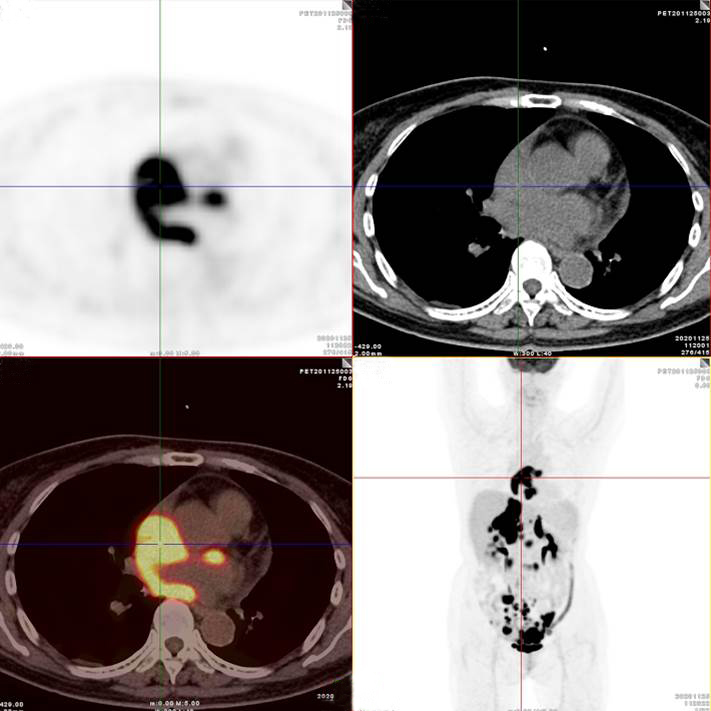

左/右心房病灶放射性攝取明顯增高